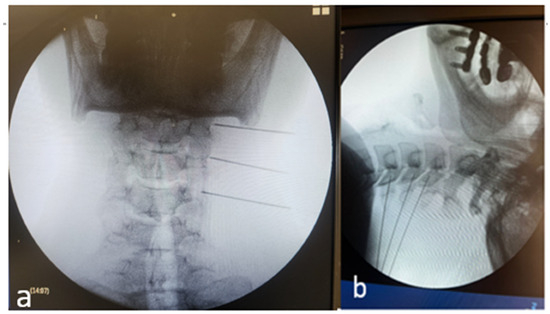

2.3.2. Fluoroscopy (FL)-Guided MBB/RFA

Procedures were performed using a mobile C-arm with low-dose protocols, in line with the As Low As Reasonably Achievable (ALARA) principle. The lateral mass was targeted in the anteroposterior and lateral projections using osseous landmarks (Figure 2). The needle/RF equipment was identical to that used for US. Intravascular or intra-articular injection was excluded with iodinated contrast, followed by optional sensorimotor stimulation. Radiation exposure metrics—fluoroscopy time (min), dose–area product (DAP, Gy·cm2), and air kerma (mGy)—were recorded directly from console logs, and device calibration information was documented [8].

Figure 2.

Fluoroscopy-guided cervical medial branch intervention. (a) Anteroposterior fluoroscopic view demonstrating alignment of the cervical vertebral bodies and identification of the target levels prior to needle advancement. (b) Oblique fluoroscopic view showing correct needle placement along the lateral aspect of the cervical articular pillars at the target levels (C3–C6), consistent with standard technique for cervical medial branch block or radiofrequency procedures.